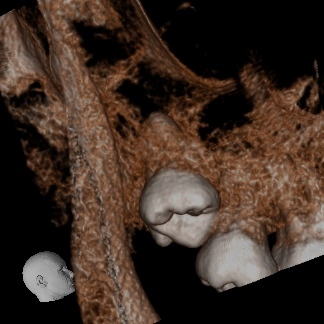

レントゲン・CTを確認すると、親知らずは深い位置で埋伏しており、歯根の一部が上顎洞に入り込んでいる可能性がありました。

今回のケースでは、CT画像で位置を正確に把握し、愛護的に処置を行ったため、抜歯後に上顎洞との交通は認められませんでした。

今回のようにCTでの事前確認と、愛護的な抜歯操作を行うことで、安全に処置を完了することができます。